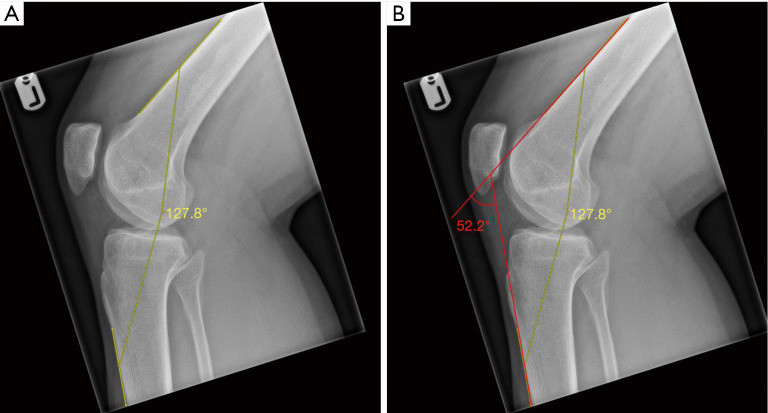

背景:活动范围(ROM)是骨科患者评估的一个重要方面。它可以通过确定患者在屈伸极限时所能达到的膝关节屈曲角(KFA)来测量膝关节的活动范围。与任何测量一样,所用方法的准确性和可靠性决定了其有效性。就 KFA 评估而言,磁共振成像(MRI)扫描与目前的黄金标准 X 光片相比,其一致性仍是未知数。本研究旨在评估和比较 X 光和核磁共振成像扫描测量 KFA 的可靠性:这项研究包括 80 名患者(94 个膝关节),他们因不同的膝关节病变前往膝关节专科门诊就诊,并接受了 X 光和核磁共振成像扫描。由两名训练有素的观察者分别在两个不同的时间点(相隔 8 周)测量侧位和 T1 加权矢状位成像视图(分别)的 KFA。然后对数据进行统计分析,并使用类内相关系数(ICC)计算观察者内部和观察者之间的可靠性:结果:X 射线的观察者内可靠性为 0.96(Pvs.16.8°),磁共振成像数据的观察者内可靠性为 0.96(P=0.022)。在这方面,X 光测量结果(46.4° 对 45.6°)无明显差异(P=0.182):结论:X 射线和磁共振成像都能以极高的可靠性测量 KFA。结论:X 射线和磁共振成像都能以极高的可靠性测量 KFA,但总体而言,X 射线测量优于磁共振成像测量,这主要是因为屏幕上可见图像的视野更大,更容易识别测量 KFA 所需的解剖标志。

Methods: This study included 80 patients (94 knees) who had attended a specialist knee clinic due to varying knee pathologies and undergone both X-ray and MRI scans. Lateral and T1-weighted sagittal imaging views (respectively) were used to measure KFA by two trained observers independently at two separate time points, 8 weeks apart. The data was then statistically analysed and intra- and inter-observer reliability calculated using the intraclass correlation coefficient (ICC).